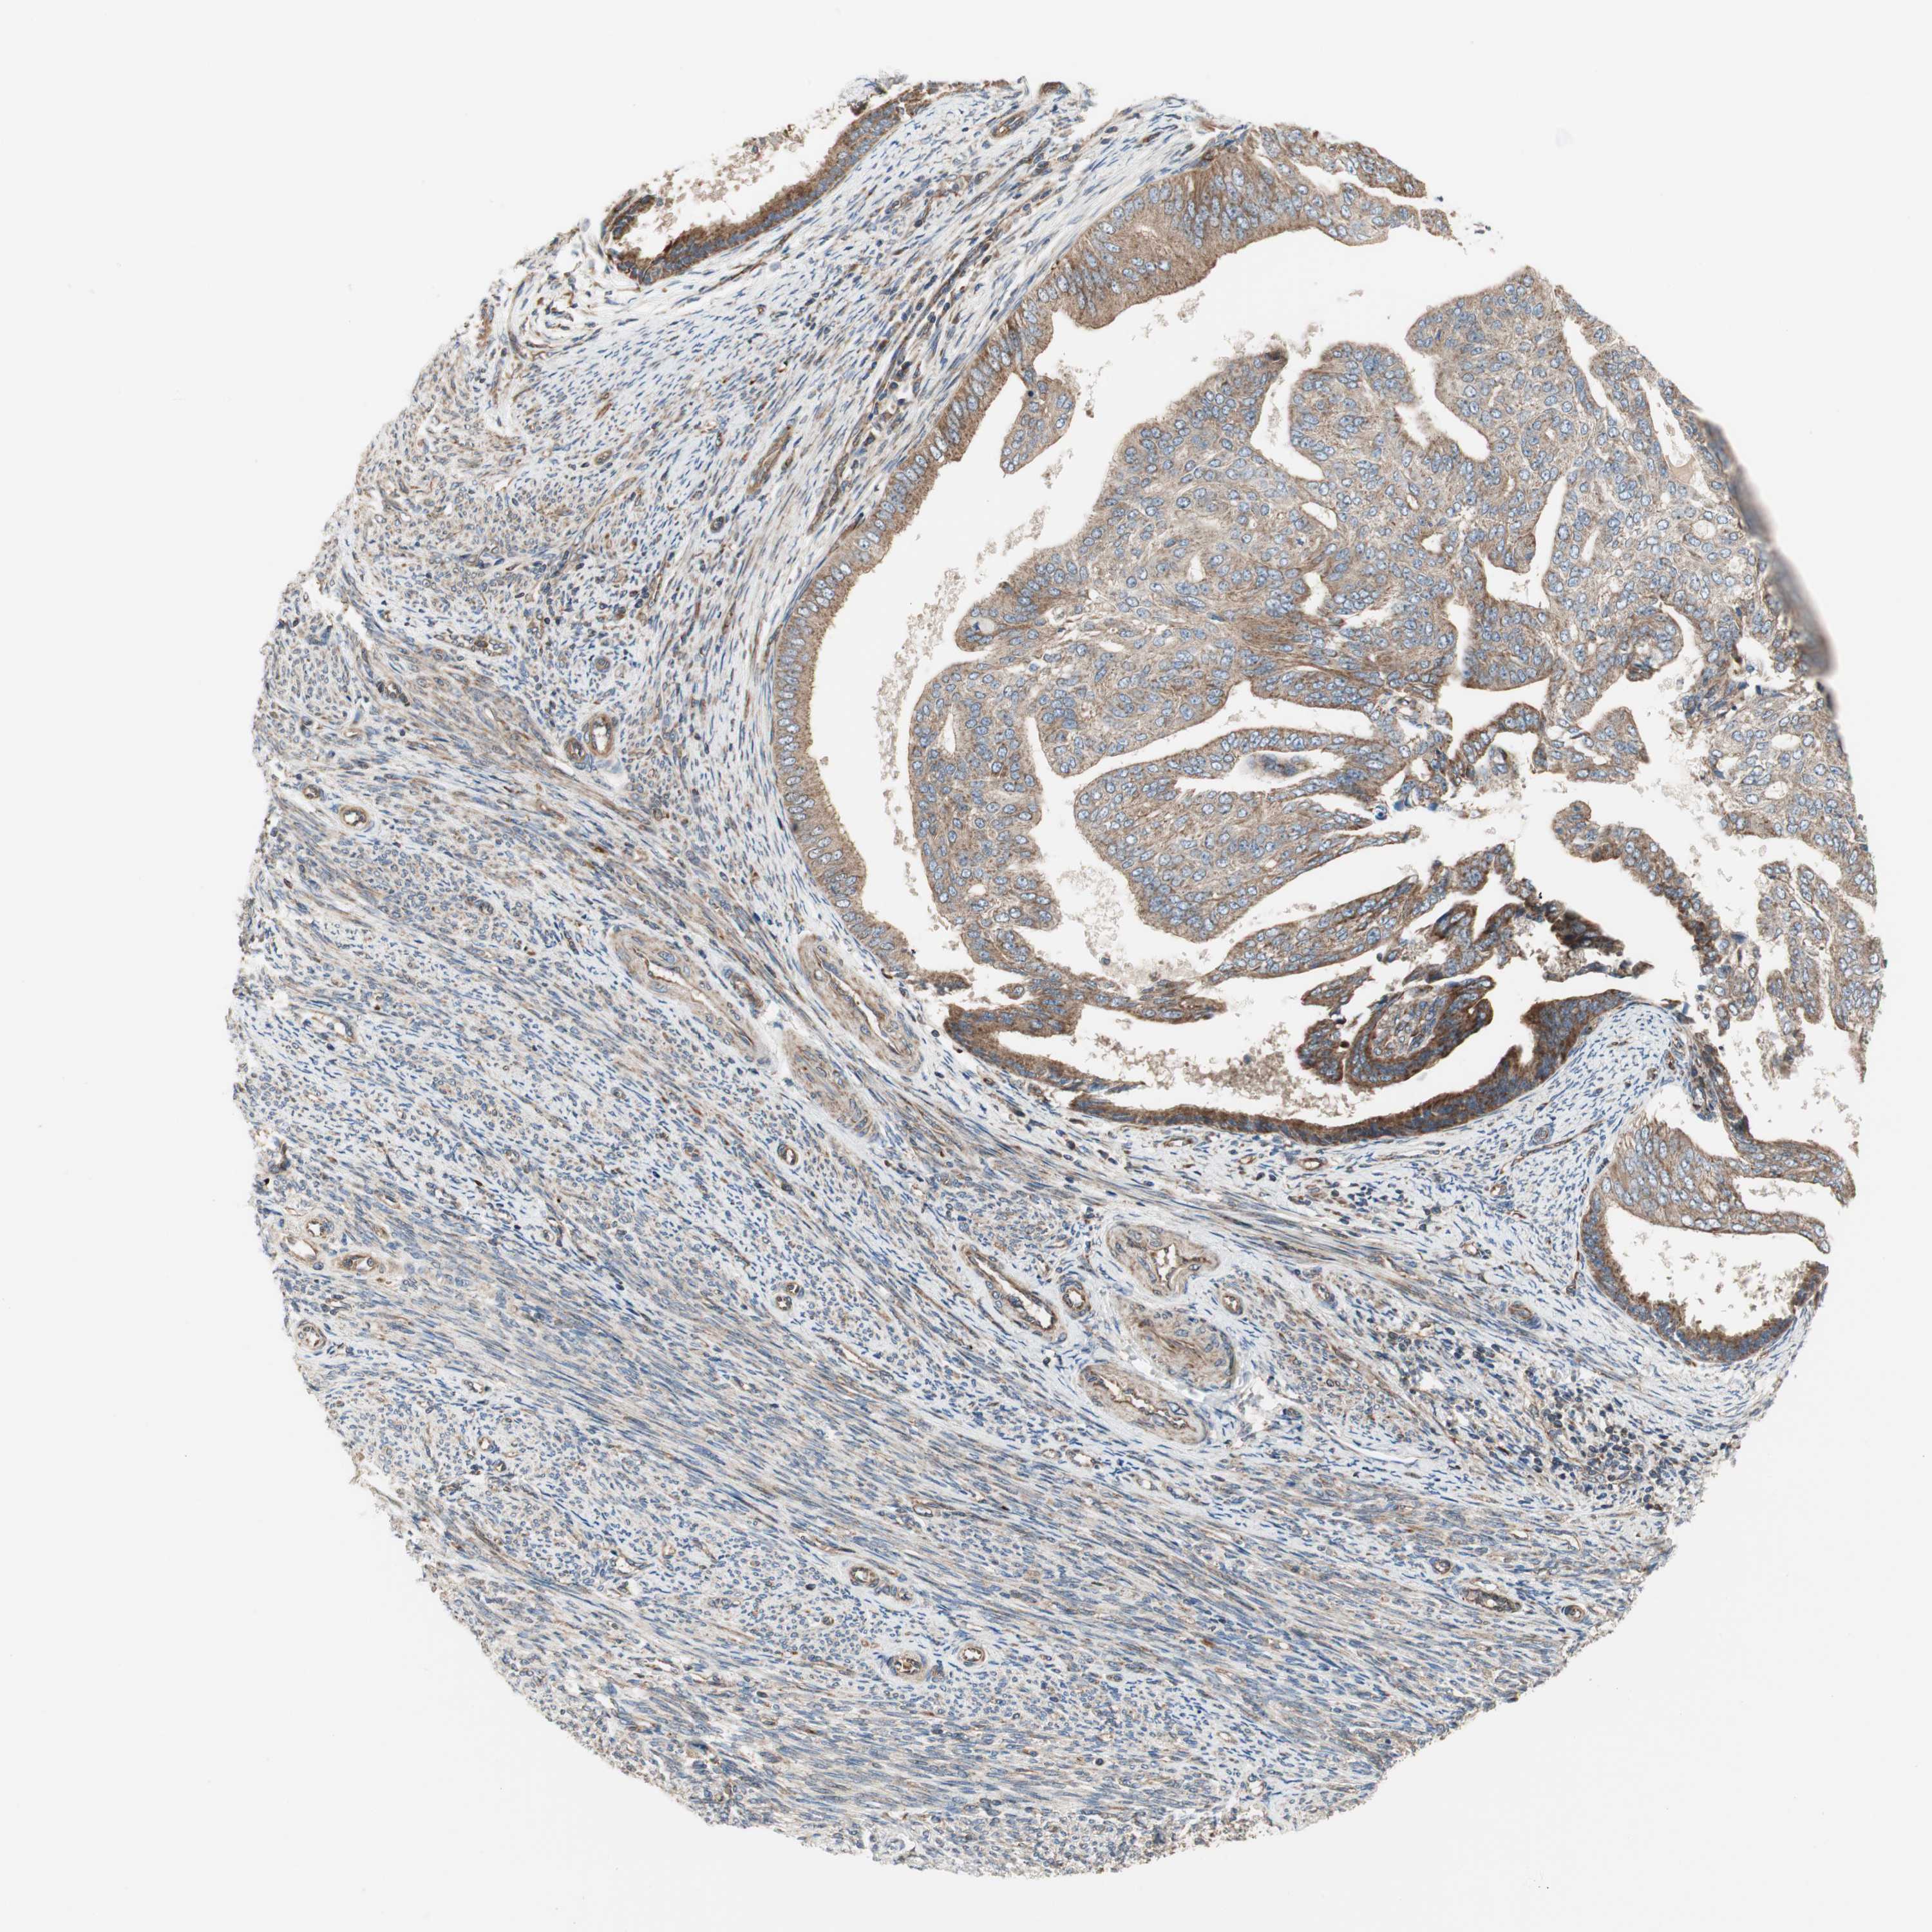

ENDOMETRIAL CANCER - Protein expressioni

A mouse-over function shows sample information and annotation data. Click on an image to view it in a full screen mode. Samples can be filtered based on level of antibody staining by selecting one or several of the following categories: high, medium, low and not detected. The assay and annotation is described here.

Note that samples used for immunohistochemistry by the Human Protein Atlas do not correspond to samples in the TCGA dataset.

Antibody stainingi

Antibody staining in the annotated cell types in the current human tissue is reported as not detected, low, medium, or high, based on conventional immunohistochemistry profiling in selected tissues. This score is based on the combination of the staining intensity and fraction of stained cells.

Each image is clickable and will lead to virtual microscopy that enables deeper exploration of all samples and also displays staining intensity scores, fraction scores and subcellular localization as well as patient and tissue information for each sample.

Antibody HPA007301

Staining

High

Medium

Low

Not detected

Intensity

Strong

Moderate

Weak

Negative

Quantity

>75%

75%-25%

<25%

None

Location

Nuclear

Cytoplasmic/membranous

Cytoplasmic/membranous,nuclear

Adenocarcinoma, NOS